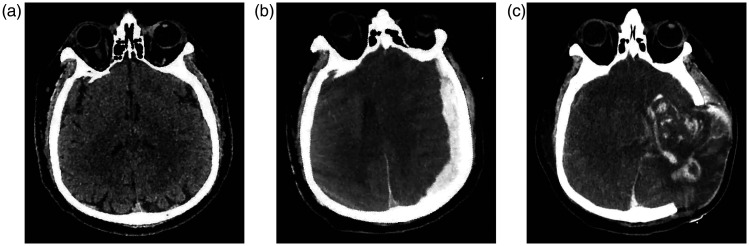

本病例详细介绍了一名50多岁、体重90公斤的男性患者,他曾前往非洲布基纳法索旅行约1个月。他在返回中国重庆3天后出现发烧、头痛和全身肌痛。从患者出现症状到诊断为严重恶性疟疾和开始青蒿琥酯治疗的时间间隔为9天。尽管进行了有效的抗恶性疟原虫治疗,但患者最终死于恶性疟原虫感染并发急性硬膜下血肿引起的多器官衰竭。

This case details a male patient in his late 50s weighing 90 kg who traveled to Burkina Faso, Africa, for approximately 1 month. He developed fever, headache, and generalized myalgia 3 days after returning to Chongqing, China. The interval from the emergence of the patient's symptoms to the diagnosis of severe falciparum malaria and the commencement of artesunate treatment was 9 days. Despite effective anti-Plasmodium falciparum treatment, the patient ultimately succumbed to multiple organ failure caused by P. falciparum infection complicated by an acute subdural hematoma.